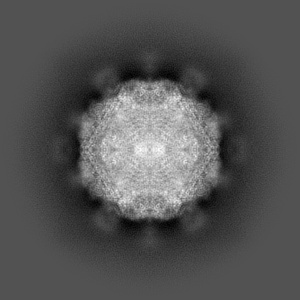

Cryo-EM structure of coxsackievirus A16 mature virion in complex with Fab h1A6.2

Single-particle3.69 Å

Sample: Coxsackievirus A16 mature virion in complex with Fab h1A6.2